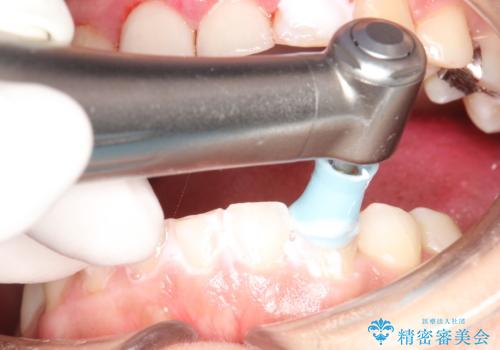

治療途中

かなり久しぶりの歯科医院との事で、全体的に古くからの歯垢・歯石が多く付着していたため、自費クリーニング(PMTC)60分コース・歯周ポケット検査(保険適応)を行いました。